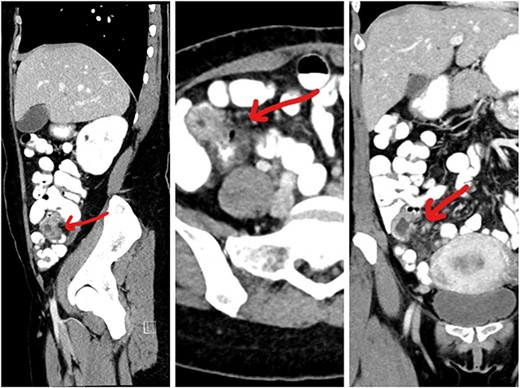

This 35-year-old nulliparous woman has been suffering from a long-standing undiagnosed abdominal pain that started 2 years earlier. The pain was colicky, localized in the right iliac fossa and seldom associated with nausea and vomiting. NO association with menstrual cycle. The previous episode was 3 months back when she was diagnosed at a center outside as a case of appendicitis with appendicular mass formation. The patient was treated conservatively at that time. This visit to the ER she presented with severe abdominal pain and subacute intestinal obstruction. The laboratories evaluations were normal. Patient had abdominal pain, nausea, vomiting, and constipation, but passing flatus for 2 days. She was vitally stable. Her abdomen was mildly distended with tenderness over the right lower quadrant but no signs of peritonitis. Patient was resuscitated and a CT scan with contrast was done to determine the nature of the obstruction (Fig. 1).CT scan showed a complex cystic lesion in the ileo caecal area with no proper delineation of the appendix. A clinical diagnosis of appendicular mass was made based on the CT findings and the patient was treated conservatively. But the patient did not respond well to conservative management and had persistent pain. She was planned for surgical intervention with a diagnostic laparoscopy and proceeded. A mass involving about 4 cm of the terminal ileum was found just about 4 inches away from the ileo caecal junction (Fig. 2). The serosa of the ileum looked normal. Appendix was found to be normal. Proximal to this intestinal lesion, there was another ileal stricture about 6 inches proximal to the ileal mass. Remaining part of the ileum and jejunum looked normal. The uterus, both ovaries, and fallopian tubes were normal (Fig. 2). Giving its close proximity to the ileocecal valve, decision was made to proceed with laparoscopic resection of the ileum including both the lesions and a limited resection of the ascending colon (Fig. 3) as discussed previously with patient.